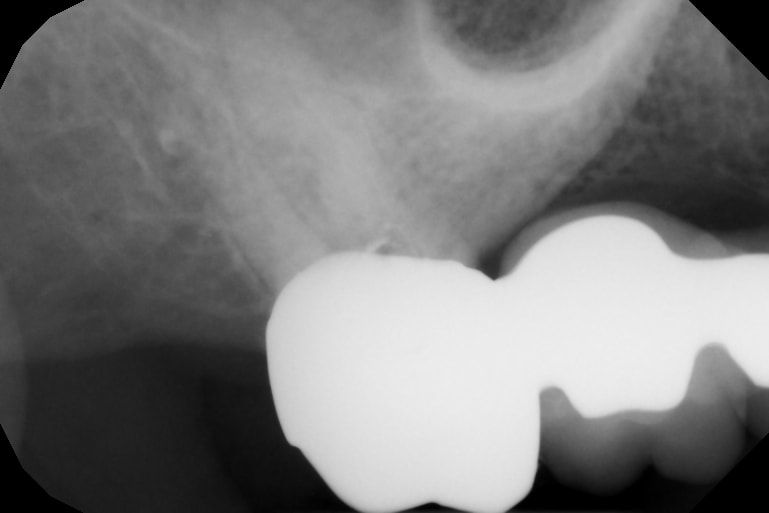

Le problème ici est la tenue de ton pilier postérieur terminal 17 car entre la perforation plancher, la cavité d’accès,

Eh ben y a plus trop de matériau dentaire pour bien tenir l’ensemble.

Je vois bien l’ensemble se désolidariser par l’arrière ou bien casser car fragile.

J'ai aussi la même appréhension que JF35. Pourquoi attendre et espérer que rien ne se passe ?

La cavité d'accès à travers ton bridge ne sera jamais refermée de manière étanche.

Tu as fragilisé ton pilier à l'aveugle, et celui-ci nécessiterait une RMIPP ou un Inlay-Core pour assurer son rôle à présent.

Puis clairement l'endo est insuffisante et il faut mieux la reprendre maintenant avant qu'un LIPOE ne s'installe.

Le pilier n'est pas autantbfragilisé que ne pourrait laisser penser la rx

Un tenon ou un IC compliqué à mettre en oeuvre à travers la couronne

A ta décharge, si j'ose, la dent etait deja limite ou meme deja en furcation., C'etait sportif de conserver cette 17....

difficile d'evaluer avec les 2 radios donnees et ces 2 incidences totalement differentes